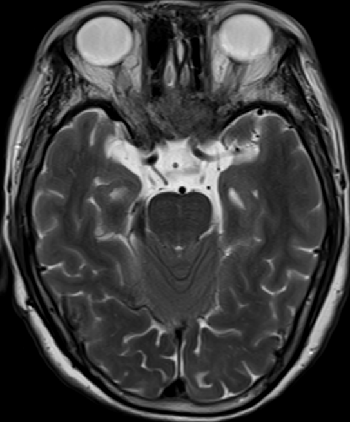

2015-4-1 MRI

2015-4-1